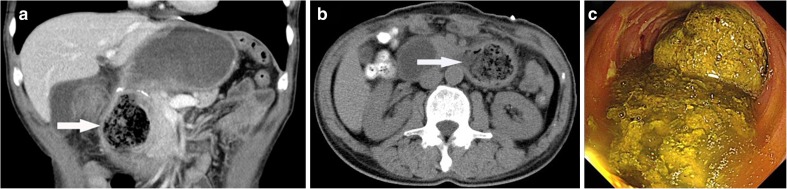

In this report, we draw special attention to a 66-year-old man with a large duodenal persimmon phytobezoar after distal gastrectomy with Billroth I reconstruction for gastric cancer. However, he complained of intermittent epigastric discomfort, acid regurgitation, and occasional vomiting with green grass gastric contents after eating dried persimmon on May 2, 2015. His symptoms greatly improved after vomiting, so he made nothing of the illness. On May 5, 2014, he was referred to our hospital due to his aggravated epigastric distention. On admission, his vital signs were stable with a blood pressure of 128/76 mmHg and a heart rate of 83 beats/min and chest and cardiac findings were unremarkable. The abdomen was supple without masses or organomegaly, and the abdominal sounds were normal, but there was moderate epigastric tenderness. On examination, the abdominal computed tomography (CT) scan showed a well-defined, oval, non-homogeneous mass in the horizontal portion of the duodenum (Fig. 1a, b). The following esophagogastroduodenoscopy (EGD) showed lots of dark green gastric juice stored in the gastric remnant, slightly hyperemic gastric mucosa, mild gastroduodenal anastomoses hyperemia erosion, and a very huge phytobezoar with a regular surface in the duodenum which caused local obstruction (Fig. 1c).

Fig. 1.

a, b CT scan showing a well-defined, oval, non-homogeneous mass in the horizontal portion of the duodenum (white arrow). c EGD examination revealed dark green gastric juice stored in the gastric remnant and a very huge bezoar with a regular surface in the horizontal portion of the duodenum